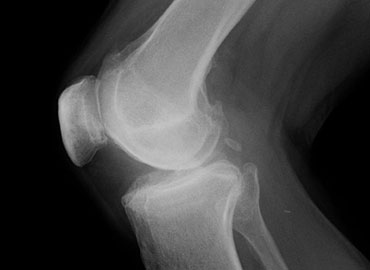

Before and After

Image Gallery

What is a knee replacement?

A knee replacement involves removing the worn joint surfaces from the top end of the shin bone and the bottom end of the thigh bone and sometimes the under surface of the knee cap. Metal and plastic components are cemented into the bone to fill the gap.